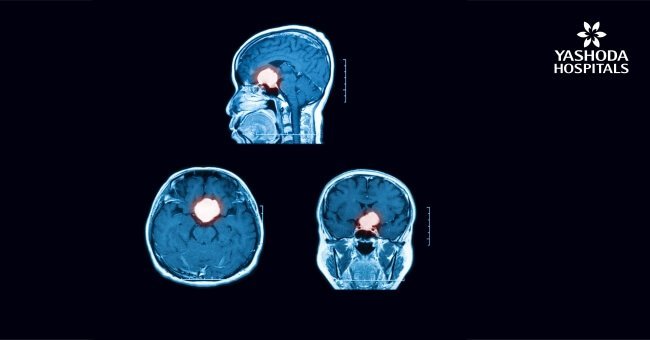

- Brain imaging: A CT scan or brain MRI scan can help the doctor to determine the size and location of the tumour

Pituitary tumours are abnormal growths in the pituitary glands. They may cause overproduction or low levels of pituitary hormones. Most pituitary tumours are noncancerous growth and remain confined within the pituitary gland. These are known as an adenoma. Pituitary adenomas can be classified as 2 types based on their sizes

- Microadenoma, when the tumour size is <1 cm. Most pituitary adenomas are microadenomas

- Macroadenoma, when the tumour is >1 cm in size